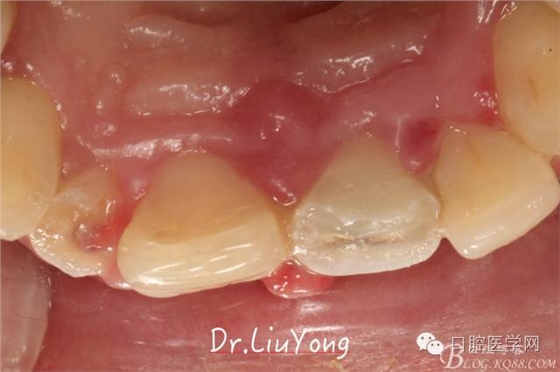

骨塊固定兩周后復(fù)查,如上圖:

松動(dòng)牙固定一月后拆除,A1-B2無(wú)明顯動(dòng)度,但牙齦紅腫加重,給予全口齦上下潔治刮治術(shù),上藥,醫(yī)囑加強(qiáng)口腔衛(wèi)生,氯己定漱口液含漱。